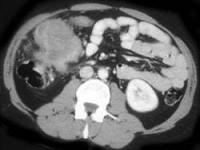

问题 男,42岁,左下腹可触及一长条形肿块,结合图像,最可能的诊断是 ( )

选项 A.结肠间质瘤 B.结肠转移瘤 C.结肠淋巴瘤 D.假膜性肠炎 E.结肠癌

答案 C